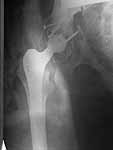

Dear All, A colleague of mine from another hospital requests opinion. A female 39 years old was operated ~1 year ago - right side THA for hypoplastic hip. Yesterday she was going to the hospital for THA of the second hip but got involved in a car accident. She admitted with right acetabular and left rami fractures (images attached). Also transverse fracture of the right distal femur. Seeking your advice regarding the acetabular fracture. THX!